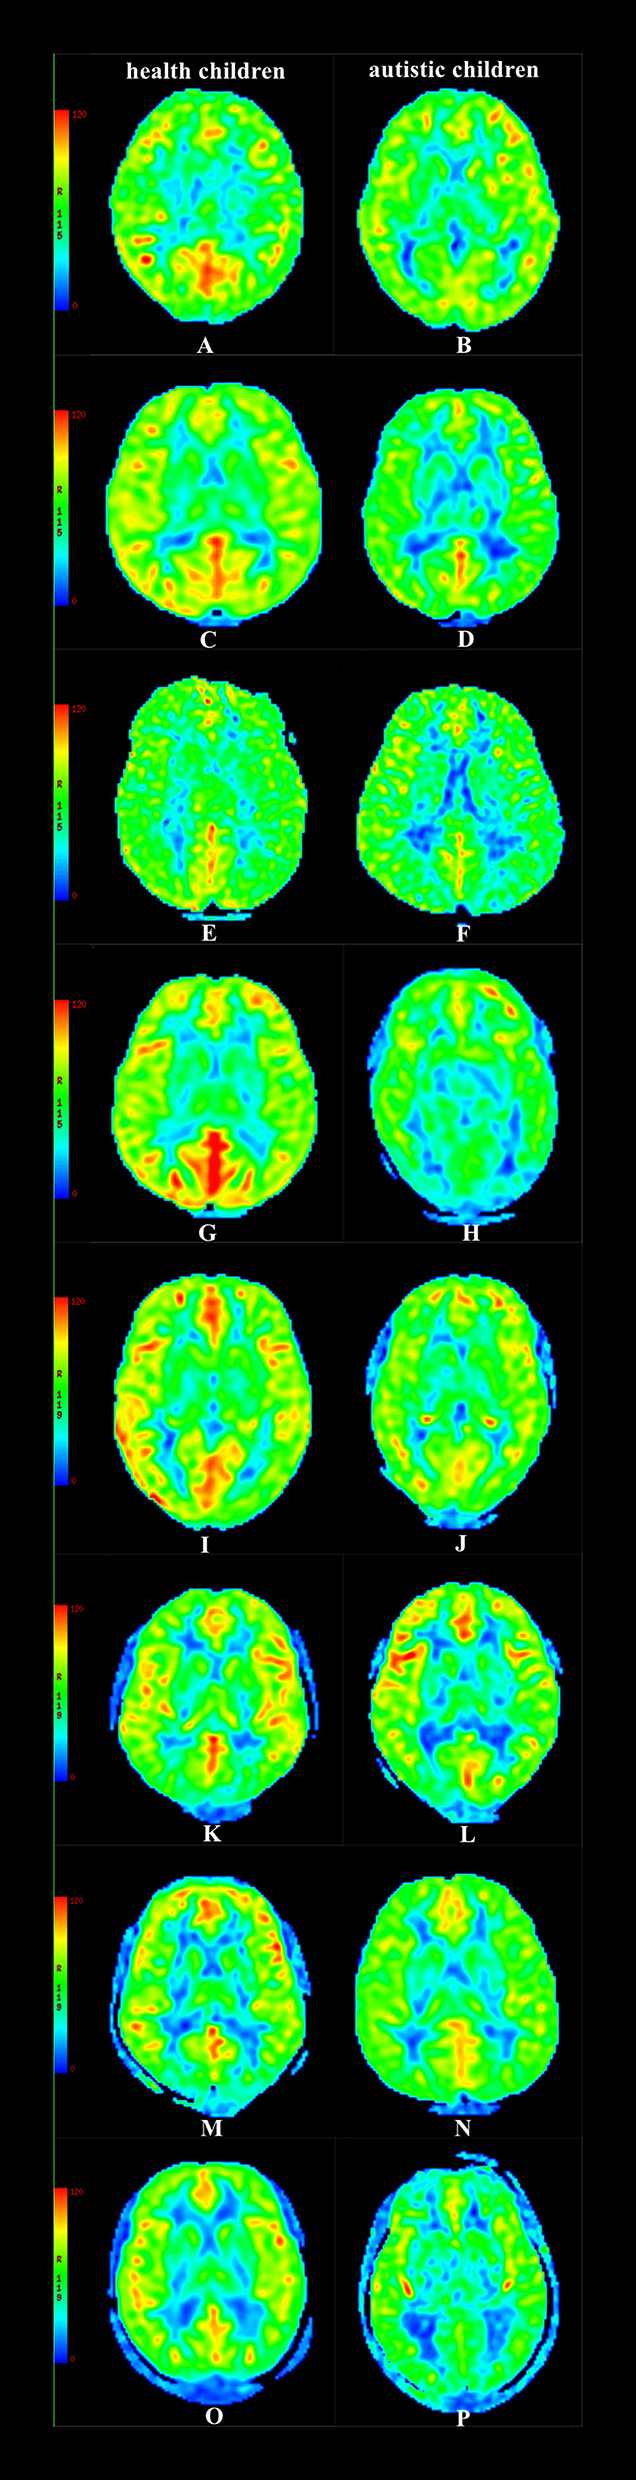

Figure 4

CBF maps (A) Male, 2.3 y, healthy children. (B) Female, 2.4 y, autistic children. (C) Male, 3.3 y, healthy children. (D) Male, 3.6 y, autistic children. (E) Female, 4.5 y, healthy children. (F) Male, 4.4 y, autistic children. (G) Male, 5.6 y, healthy children. (H) Male, 5.4 y, autistic children. (I) Female, 6.9 y, healthy children. (J) Male, 6.7 y, autistic children. (K) Male, 9.7 y, healthy children. (L) Male, 9.9 y, autistic children. (M) Male, 12.7 y, healthy children. (N) Famle, 12.8 y, autistic children. (O) Male, 16.8 y, healthy children. (P) Male, 16.6 y, autistic children.

In the group with 2-year-old children, the CBF values of the temporal lobe, hippocampus, and putamen in children with autism were lower than those in healthy children (P < 0.05); in the group containing 3-year-old children, the CBF values of the frontal lobe, temporal lobe, hippocampus, and putamen in children with autism were lower than those in healthy children (P < 0.05); in the group with 4-year-old children, the CBF values of the temporal lobe, frontal lobe, thalamus, hippocampus, putamen, and caudate nucleus in children with autism were lower than those in healthy children (P < 0.05); in the group containing 5-year-old children, the CBF values of the temporal lobe, thalamus, hippocampus, putamen, caudate nucleus, substantia nigra, and red nucleus in children with autism were lower than those in healthy children (P < 0.05); and in the group with 6–18-year-old subjects, the CBF values of the frontal lobe, temporal lobe, thalamus, hippocampus, caudate nucleus, substantia nigra, and red nucleus in children with autism were lower than those in healthy children (P < 0.05) (Table 2, Figures 3, 4).